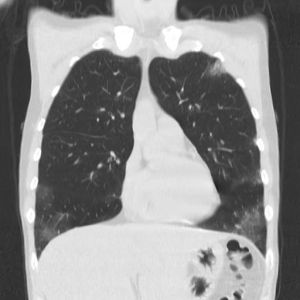

Os achados mais comuns na Tomografia Computadorizada do Tórax (TC) em pacientes com GEPA consistem em áreas de consolidação ou atenuação em vidro fosco, heterogêneas, de distribuição lobular, bilaterais, periféricas, migratórias, associadas com doença das vias aéreas (Figura 2).38 Pode haver espessamento septal interlobular, reticular intersticial ou reticulonodular.39

Figura 2 – Jovem de 30 anos com GEPA, com tosse não produtiva crônica, febre baixa, relato de asma há dez anos. Tomografia computadorizada de alta resolução (TCAR) demonstrando infiltrados heterogêneos, bilaterais, em vidro fosco na periferia de ambos os pulmões. Cortesia de

Shervin Sharifkashani. From the case https://radiopaedia.org/cases/98647?lang=us">rID: 98647

A TC de tórax é útil para diferenciar a GEPA de asma grave. Um estudo revelou que a pontuação radiológica dos pacientes com GEPA foi significativamente maior em comparação aos pacientes com asma grave. Além disso, opacidades difusas em vidro fosco foram observadas em 74% dos pacientes com GEPA, enquanto apenas 18% dos pacientes com asma grave apresentaram essa característica (p<0,001).40,41